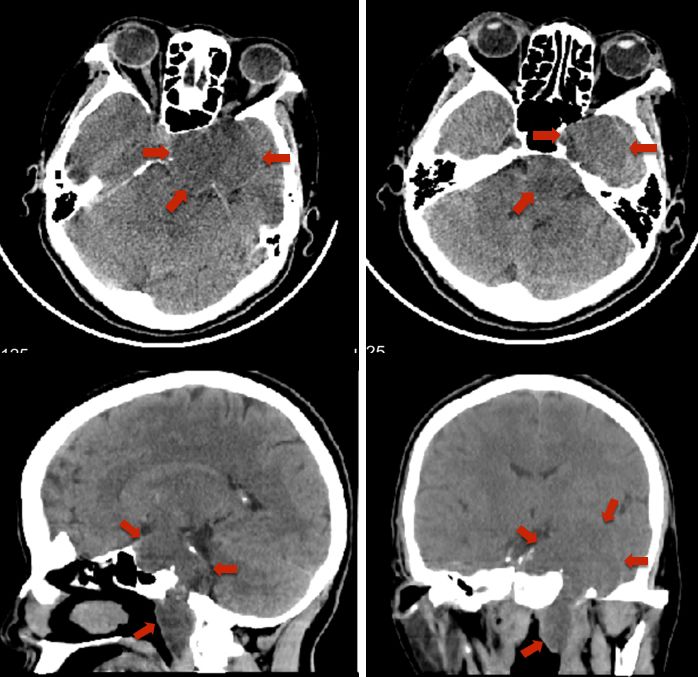

术后当日CT平扫